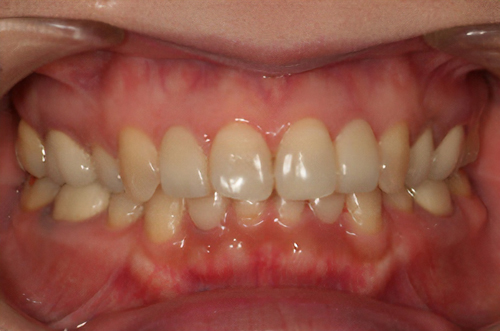

歯の形、歯並び、歯肉ラインが整う美しい口元

大掛かりな歯ぐきの手術や装置を使った矯正治療を行わずに、たった2回で歯並びをきれいに整えることができます。

BTAテクニック® とは

従来のセラミックで治すオールセラミックという被せ物や、セラミックを張り付けるラミネートべニアという方法に、歯科医師と歯科技工士の双方の手法と技法を癒合させることで、可能とした 歯ぐきのラインを2回の来院で、綺麗に仕上げ、歯の見た目も審美的に出来るテクニックのことである。

BTAテクニック® 以外の一般的な治療で歯ぐきのラインを整えるには、歯ぐきを切り、骨を削る手術をすれば可能ですが、歯ぐきの治りに数か月の期間が必要です。もしくは、矯正治療によって、歯並びを改善する方法、もしくは神経を抜いて、被せ物をするしかありません。

BTAテクニック® を用いると、歯ぐきや骨への手術が必要ない為に、治療期間が短縮でき、2回の来院で完了できるメリットがある。 また、この方法を用いることで、年々歯ぐきが下がって見た目が悪くなるということが起きにくくなる。歯周ポケットと言われる溝が浅くなり、歯ブラシが容易になる。などの利点が挙げられる特殊なテクニックである。